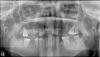

ibik Опубликовано 5 декабря, 2008 Автор Поделиться Опубликовано 5 декабря, 2008 кидаю снимки ОПГ и 2 справа сверху, там сказали интересный корень может надо делать резекцию, потянет ли такая 2-ка мост из 2х передних ... Варианты: 1) мост от 7 слева до 7 справа с депульпированием всех необх зубов 2) имплантация, но справа есть киста .... И еще так ли гигиена влияет на приживляемость имплантантов, мне сказали что зубной налет может повлиять на приживляемость .... и соответственно на сроки гарантии ... Ссылка на комментарий

Палыч Опубликовано 5 декабря, 2008 Поделиться Опубликовано 5 декабря, 2008 Варианты: 1) мост от 7 слева до 7 справа с депульпированием всех необх зубов 2) имплантация, но справа есть киста .... И еще так ли гигиена влияет на приживляемость имплантантов, мне сказали что зубной налет может повлиять на приживляемость .... и соответственно на сроки гарантии ...1. Нет2. Да, с остеопластикой.3. При плохой гигиене ни о какой импелантации речи быть не может. Сталинград, да и только Ссылка на комментарий

Максимов Опубликовано 5 декабря, 2008 Поделиться Опубликовано 5 декабря, 2008 (изменено) При всей моей любви к имплантатам...Да, протезирование на имплантатах возможно. И такой вариант будет объективно лучше с точки зрения надежности, и не только.Но. Посчитайте, сколько нужно имплантатов. Шесть - восемь? Восьми, в то же время, достаточно для протезирования при полном отсутствии зубов. А иногда и шести...С другой стороны, оставшихся зубов, конечно маловато для по-настоящему надежного мостовидного протеза. Это так. Но сделать его можно. Потому как, когда придет время протезироваться вновь, даже если все опорные зубы надо будет удалять, все равно нам понадобятся те же 6-8 имплантатов. Атрофии, которая могла бы резко снизить шансы установить имплантаты, скорее всего не произойдет. Так что - как вариант бюджетного протезирования с ограниченным сроко службы, почему нет? Лет на пять Вас усроит? Только делайте обычную металлокерамику, не золото, и не циркон. Хотите циркон - только имплантаты. Не потому, что такой мост сделать невозможно, а потому, что, повторюсь, мост - бюджетное решение, и материалы логично применить бюджетные.И еще. Не надо ничего депульпировать. Клыки и моляры, если не нужно изменять положение зубов в дуге, практически всегда можно оставить живыми... Изменено 5 декабря, 2008 пользователем Максимов Ссылка на комментарий